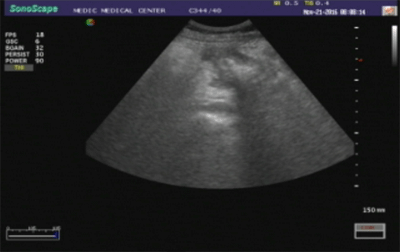

-Siêu âm doppler bụng cho thấy vùng gan (P) có hình ảnh ổ áp-xe cấu trúc echo hỗn hợp, đường kính d = 5,5cm, bờ nham nhở, kèm phù nề chủ mô gan xung quanh và tăng tưới máu nhẹ. Ngoài ra, đại tràng góc gan có hình ảnh dày vách, echo kém, d = 15mm, không hẹp lòng (Hình 1).

Hình 1. Khối áp-xe gan (P) và hình ảnh dày vách đại tràng góc gan trên siêu âm.